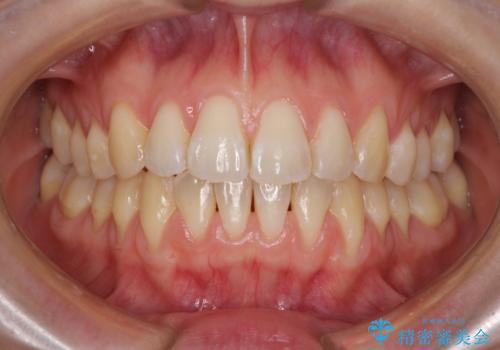

上下前歯が接触しない オープンバイトをインビザラインで改善

オープンバイト(開咬)を非抜歯インビザラインで治す